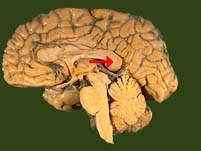

如图箭头所示为大脑哪个部位 ( )A、穹窿B、中脑导水管C、胼胝体D、透明隔E、前连合一、单项选择题

问题 如图箭头所示为大脑哪个部位 ( )

选项 A、穹窿 B、中脑导水管 C、胼胝体 D、透明隔 E、前连合 一、单项选择题

答案 C